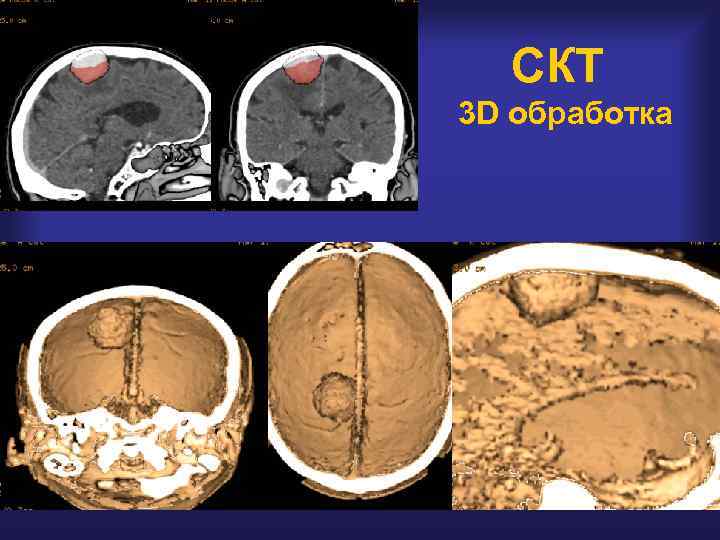

Парасагиттальная менингиома СКТ Костная деструкция

СКТ 3 D обработка

СКТ : костные ориентиры